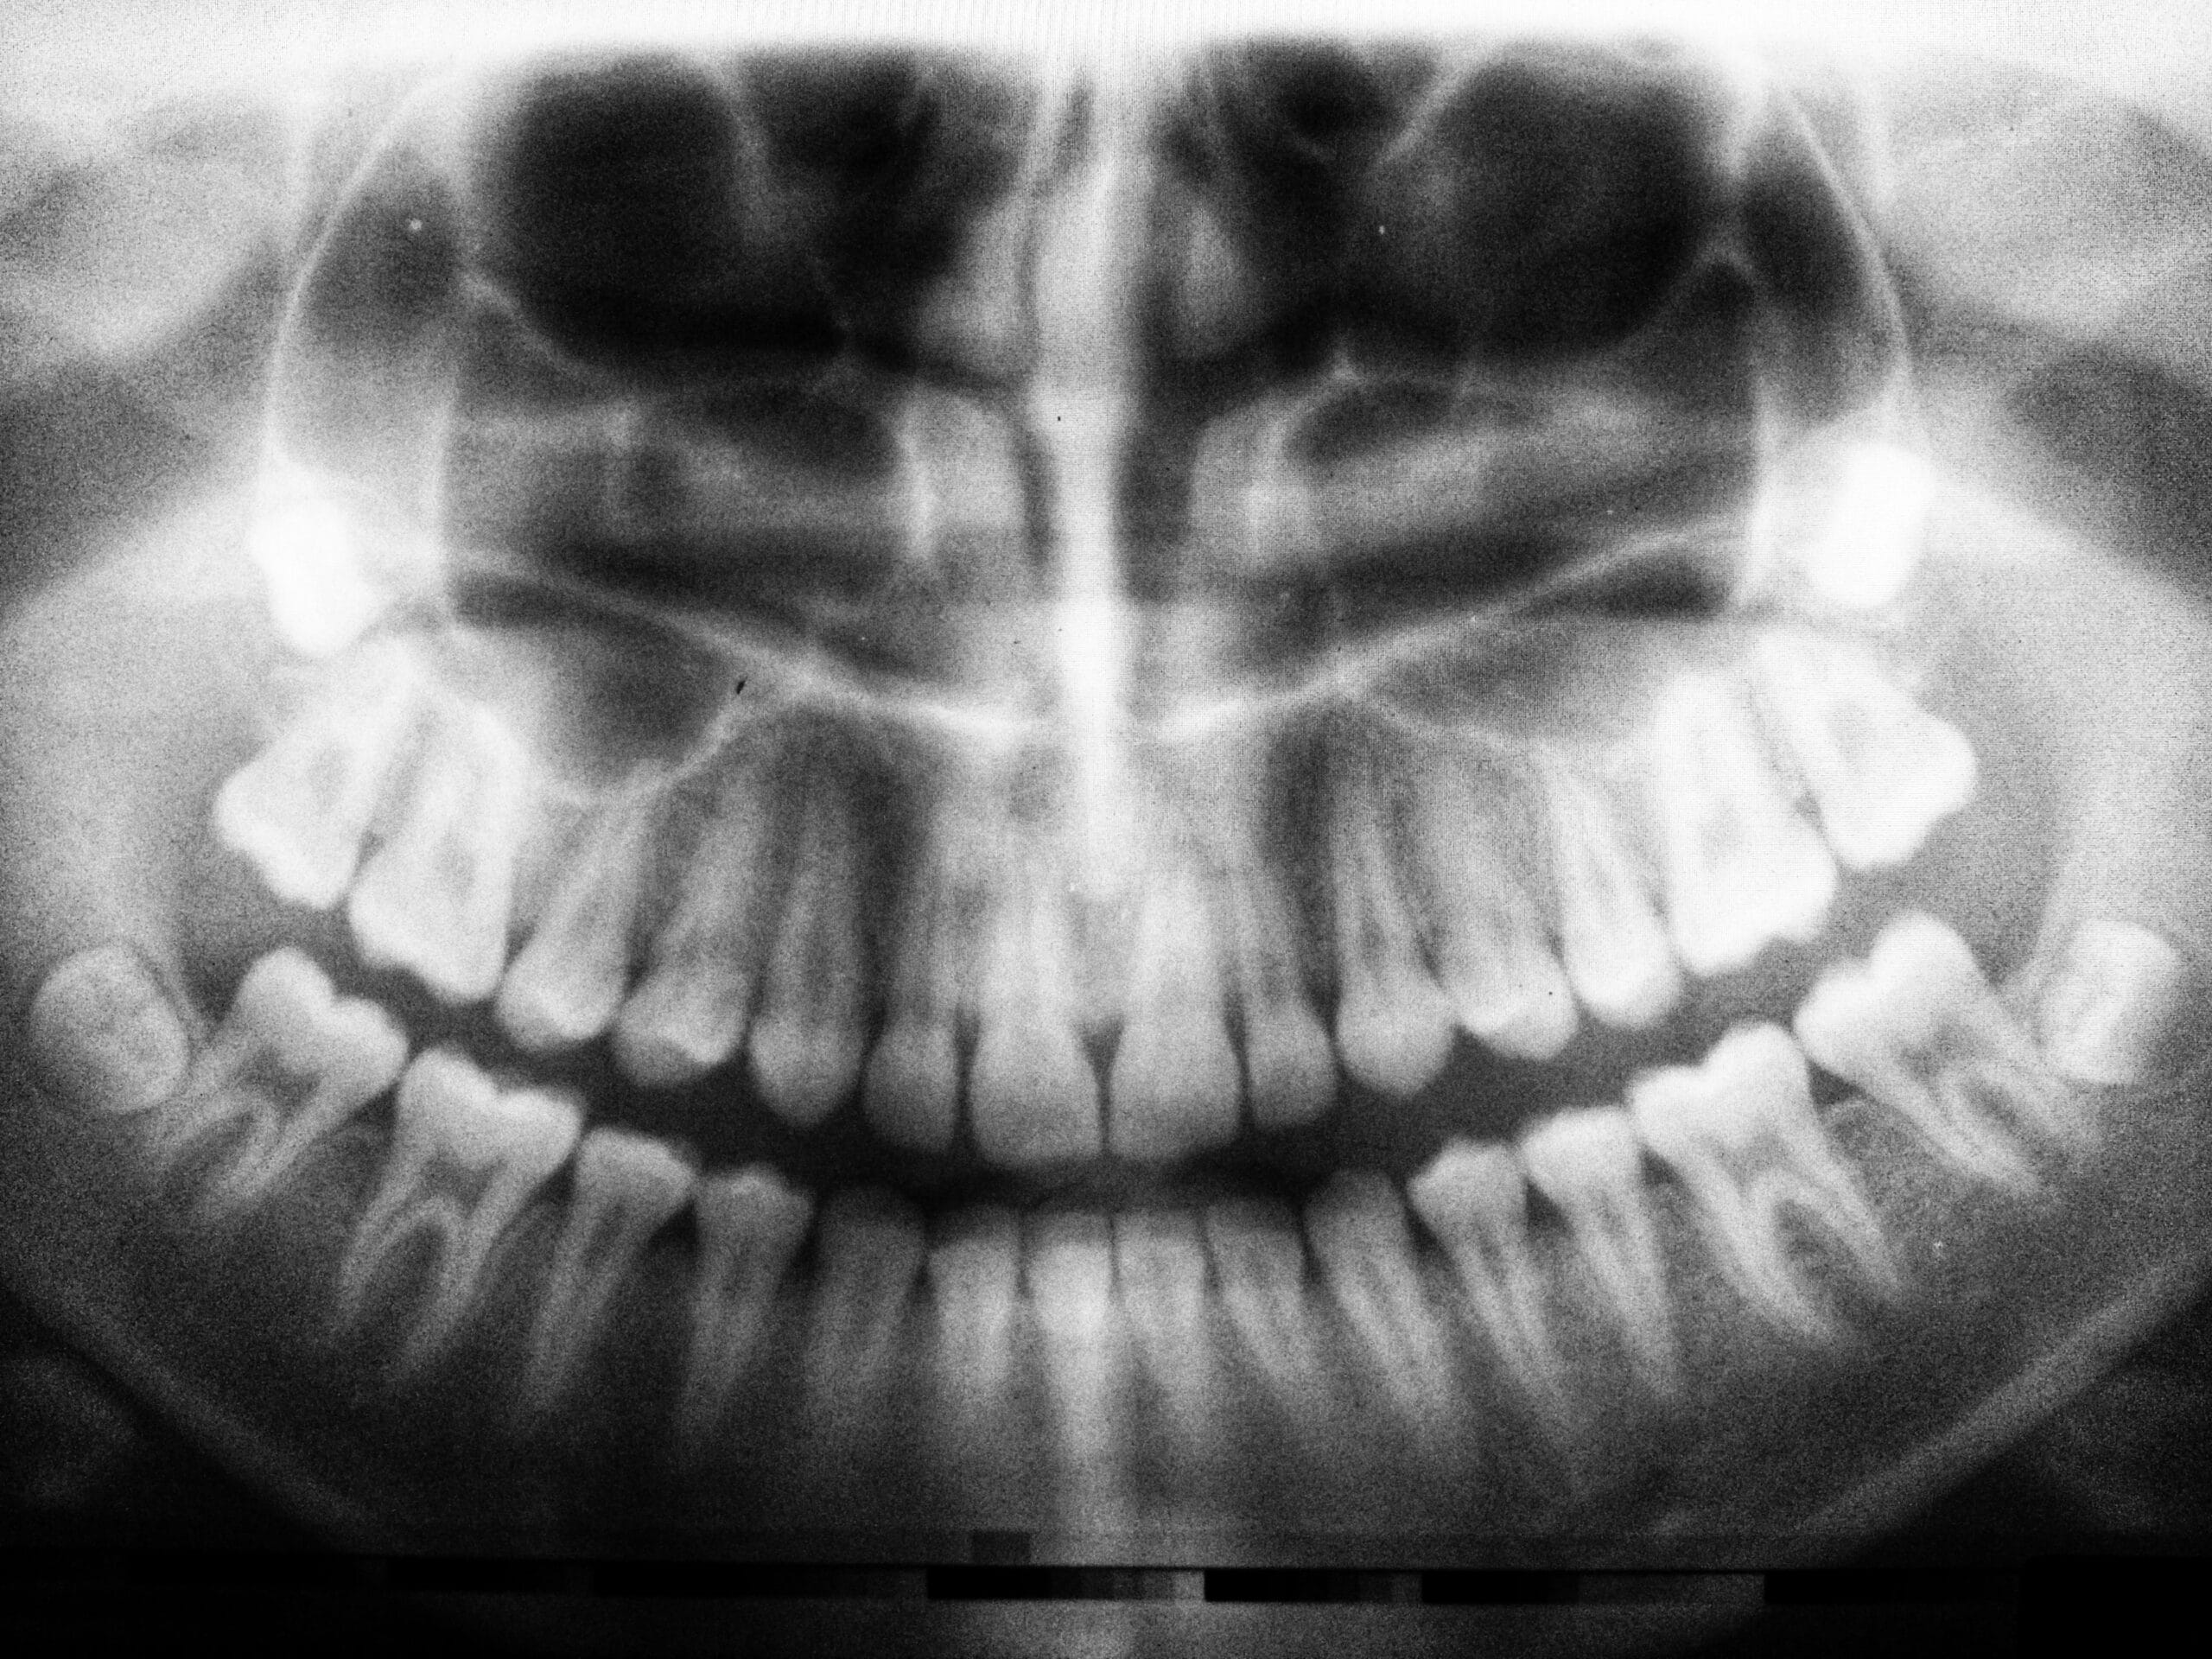

Panoramic X-Rays

Our panoramic x-ray machine is digital and allows us to check the health and position of your teeth. It also allows the dentists to see the bones of your jaw to check for disease, monitor growth or locate wisdom teeth.  Our dentists recommend that you have one taken every 5-7 years to monitor your overall oral health.  We routinely take them once a child is about 8 years old to see if they are developing normally and if all of their adult teeth are developing.  This allows us to intervene if necessary to help correct abnormalities.  Panoramic x-rays are taken before orthodontic treatment (braces) is started to plan the course of treatment.  We also take them before wisdom teeth are extracted to locate the wisdom teeth as well as the location of the nerves and sinuses to assess the risks of the procedure.  Routinely taking a panoramic x-ray helps our dentists detect problems while they are hopefully small – from impacted wisdom teeth to missing adult teeth, from cysts growing in your jaw bone to oral cancers.  These panoramic x-rays give the dentist and you a great overall view of your mouth.   Check out our blog post about panoramic x-rays for more information.